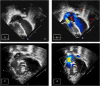

"Cases of SCMR" is a case series on the SCMR website (https://www.scmr.org) for the purpose of education. The cases reflect the clinical presentation, and the use of cardiovascular magnetic resonance (CMR) in the diagnosis and management of cardiovascular disease. The 2022 digital collection of cases are presented in this manuscript.

Keywords: Arrhythmogenic cardiomyopathy; COVID-19; Cardio-oncology; Congenital Heart disease; Coronary artery aneurysm; Hydatid disease; Hypertrophic cardiomyopathy; Metastatic disease; Myocardial. infarction; Myocarditis; Takotsubo; Vaccine associated myocarditis; Viability.